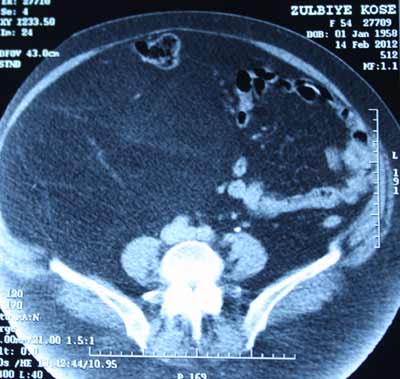

Genel Cerrahi Uzmanı Opr. Dr. Aziz Ahmet Surel, bu büyüklükte bir kitlenin tıpta nadir görüldüğünü belirterek “Hastamız karın bölgesindeki şişlik şikayetiyle bize başvurdu. Yaptığımız tahliller sonucu karın bölgesinde büyük bir kitle olduğunu belirledik. Daha sonra hasta ameliyata alındı. Ameliyatta hastanın karnından yaklaşık olarak 45 santimetreye 30 santimetre boyutlarında 15 kilogram ağırlığında bir kitle başarılı bir ameliyatla çıkarıldı. Bu kitle karın içersinde o kadar bir yer kaplamış ki normalde olması gereken bağırsaklar üçte bir alana sıkışmış vaziyetteydi. Kitleyi çıkardık hastamızı 3 gün boyunca yoğun bakımda takip ettik. Hastamız 7 gün içinde taburcu oldu. Çıkan kitleyi patolojik incelemeye gönderdik. Patolojiden çıkan sonuca göre kalan tedavi sürecini planlayacağız” dedi.